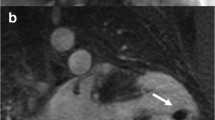

Most of our information about structural abnormalities in ARVC comes from studies in subjects with a predominant RV phenotype (Figure 1) [42]–[44]. Abnormalities in the RV in ARVC have been extensively described (reviewed in [15]). Besides global reduction in RV function and enlargement of the RV, more subtle regional disease of the RV has been variously described in the literature using a variety of terms (including focal bulges, microaneurysms, segmental dilatation, regional hypokinesis, etc.). In the current TFC, the terms “akinesia” (lack of motion) and “dyskinesia” (abnormal movement – instead of contracting in systole, that segment of myocardium bulges outward in systole) and “dyssynchronous” (regional peak contraction occurring at different times in adjacent myocardium) are used for all imaging modalities (CMR, echocardiography and angiography) to describe regional wall motion abnormalities in ARVC. Microaneurysms are not explicitly described in the revised TFC for CMR; overuse of this finding was considered by the Task Force members to be misinterpreted by CMR physicians resulting in false positive diagnoses. However, microaneurysms are characterized by regional akinesia or dyskinesia in the revised criteria.

Four-chamber (top panels) and short-axis (bottom panels) bright blood images in an ARVC subject with predominant right ventricular abnormalities. End-diastolic images are shown in the left panels, end-systolic images in the right panels. Note subtricuspid dyskinesia in the end-systolic four-chamber image (arrow), and right ventricular free wall aneurysms (i.e. both systolic and diastolic bulging) in the short-axis image (arrows).

The location of regional wall motion abnormalities of the RV was not addressed in the revised TFC. We now recognize that the distal RV (from the moderator band to the apex in long axis views) shows highly variable contraction patterns in the normal individual. Therefore in ARVC, we emphasize the significance of regional wall motion abnormalities in the subtricuspid region. An excellent example of this is the so-called “accordion sign” that represents a focal “crinkling” of the myocardium (Figure 2) [45],[46]. In terms of TFC, the accordion sign is due to a small region of highly localized myocardium with dyssynchronous contraction.

Regional contraction abnormality in the subtricuspid region. End diastolic (left) and end systolic image (right) show the so-called “accordion sign” in an ARVC mutation carrier. Regional dyssynchronous contraction in the subtricuspid region is a readily recognized qualitative pattern of abnormal RV contraction.